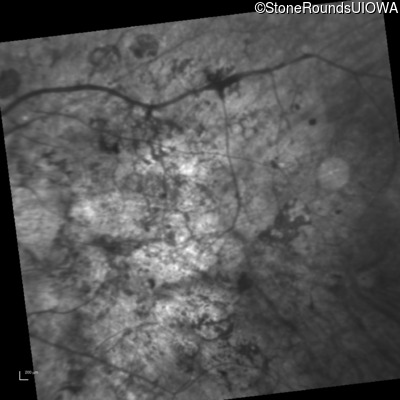

Age at visit: 33 years